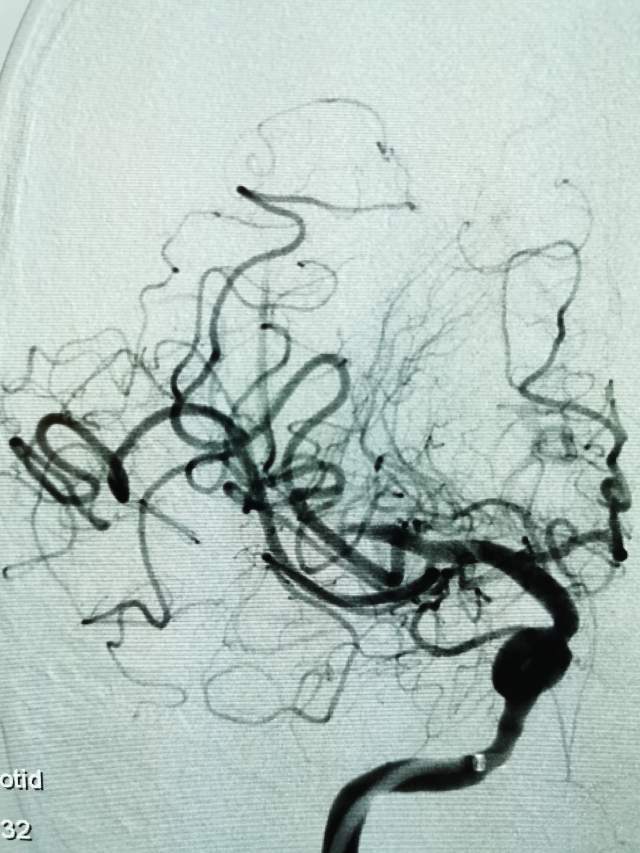

河南信阳帅哥,一个半月前突然出现左侧肢体肌力乏力、认知功能大幅下降、反应迟钝,在当地多家医院按照“脑梗塞”诊治后,症状未能缓解,仍呈进行性加重。经推荐转至我院寻求治疗,术前谈话之后,疫情期间,家里有急事需要处理,唯一的陪人回家了……。今日为患者手术,术中发现右侧大脑中动脉的一个分支出现多节段、长节段的夹层,血流仅剩断断续续的一条线,在血中飘摇,随时存在血管完全闭塞,脑梗塞继续加重,重者可能危及患者生命……,术中正确辨别真腔(误判后果严重),顺利打通重建血管,血流恢复……,手术只是整个治疗过程的一小部分,围手术期仍需要再接再励,帮助患者渡过风险期~~~

最后答案:血管夹层是导致青壮年自发性脑梗塞的罪魁祸首